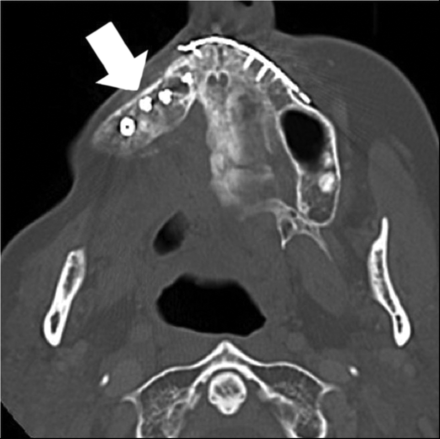

Axial imaging of a normal ICFF demonstrating a thick sheet of bone with a hyperattenuated cortex and intermediate attenuation of the trabecular surface. An osteotomy site is demonstrated and filled with corticocancellous bone (arrow). Images were obtained in the immediate postoperative period. Left cheek prominence is an expected immediate postoperative finding in the flap setting. Normal cheek cosmesis will be obtained over time.

On postoperative CT imaging, the osseous component of the ICFF appears as a thick sheet of bone with 2 cortical layers and a sclerotic trabecular surface. The bone has a hyperattenuated cortex and intermediate attenuation of the trabecular layer (Fig 4). The osseous component of the flap may be used to restore the normal osseous boundaries of the maxilla, alveolus, orbital rim, and pyriform aperture. The ilium is thickest at the spine and narrows posteriorly but appears on 2D imaging as a uniformly thick sheet of bone.17